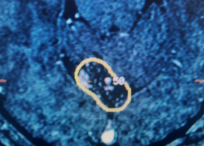

Dr. Brisman is proficient in the use of minimally-invasive, neurosurgical procedures including:

- Stereotactic Radiosurgery

- Gamma Knife®

- CyberKnife®

- Novalis Tx®

- Brain Tumors

- Gliomas